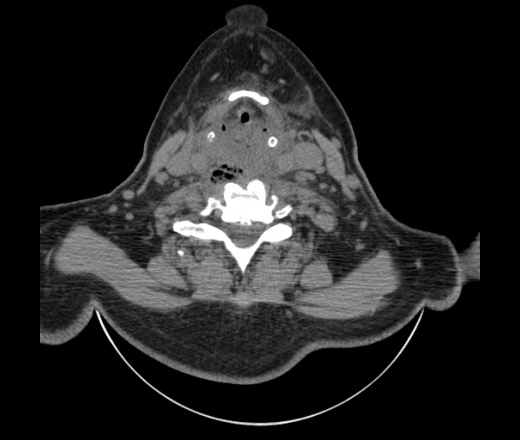

Женщина поступила в х/о спустя 4 дня после того как при употреблении карася подавилась костью.

Наличие газа в средостении на протяжении тел С2-С6 (медиастинальна эмфизема); рыбная кость на уровне тела С6.

При всем уважении, но говорить о медиастинальной эмфиземе, оценивая мягкие ткани шеи, как-то слишком резко. На мой взгляд, это ретрофарингеальное пространство.

Эвакуировали почти 100мл гноя. Но кость не смогли найти. Думаю что она даст дальнейшее ослоднение. Эндоскопически за черпалонадгортаной звязкой не смогли зайти в пищевод, все мягкие ткани отечные, просвет пищевода сдавлен. По всей видимости параэзофагеальная клетчака тоже задействована. Эмпиема, если ее можно так назвать, незнаю как правильно дошла до уровня яремной вырезки. Чем закончиться напишу. Ждем медиастинита.

Согласен с Вами; конечно, наличие газа в клетчатке ретрофарингеального пространства (затмение с опечаткой..). К сожалению, процесс "продвигается" к медиастиниту. Но почему никто, не отмечает наличие рыб. кости; или это для Всех очевидно?

Кость то мы сразу выявили, размеры где то 17*2мм, но ее так и не получается найти в этой каше